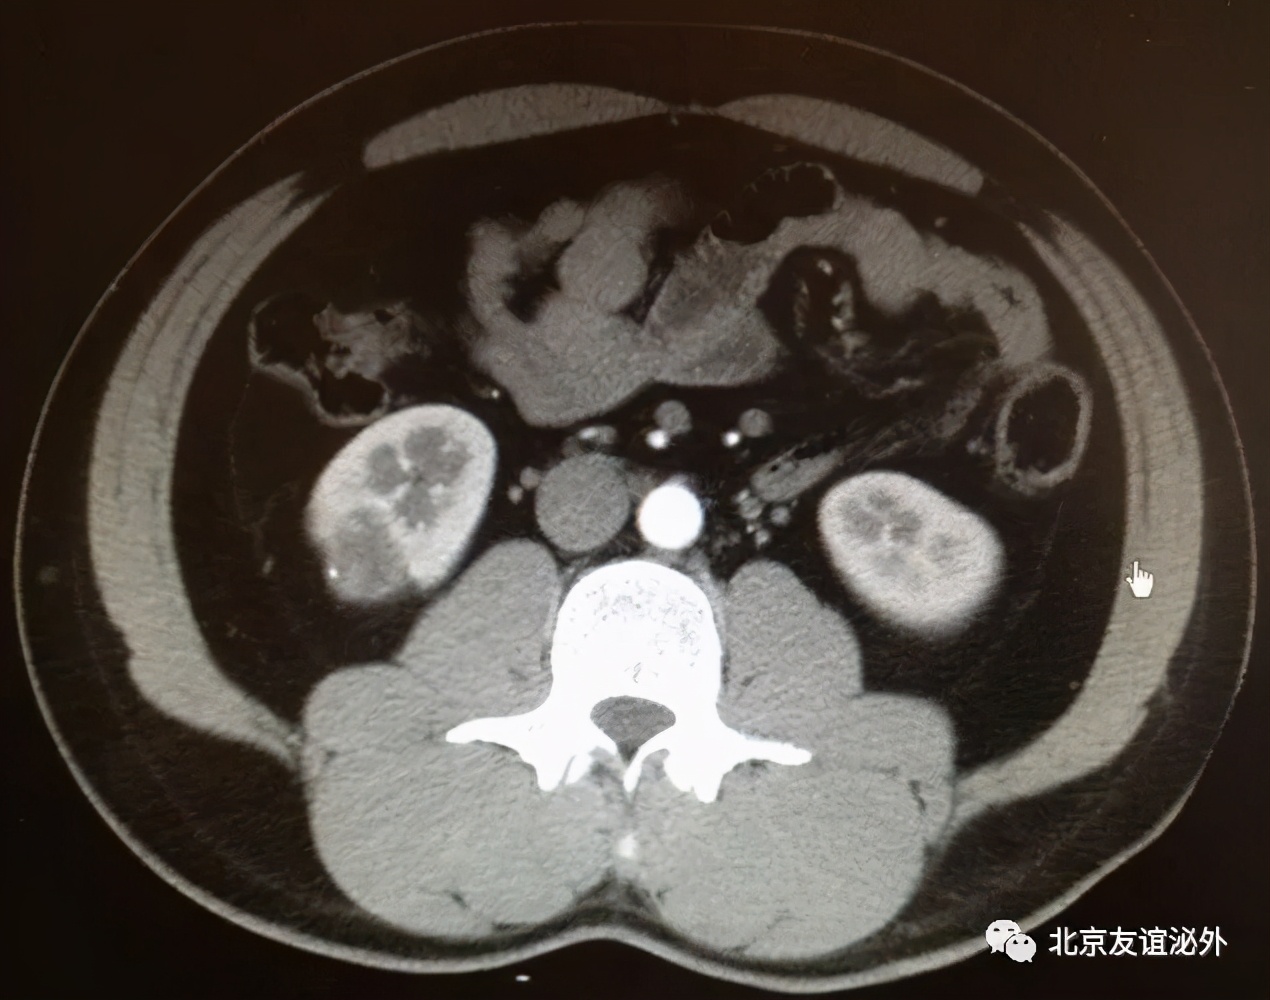

图3. Bosniak II级良性囊肿(囊肿内少量细小分隔)